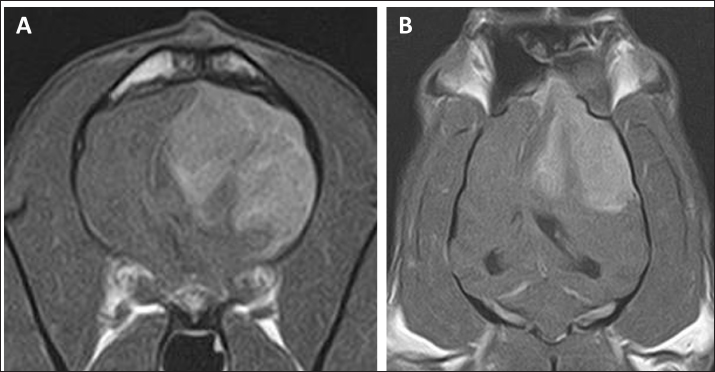

On day 99, the patient presented with acute onset of somnolence and recumbency. Cerebral infarction was suspected because the entire right cerebral hemisphere and part of the thalamus showed high signal intensity on T2WI and FLAIR images, high signal intensity on diffusion weighted Imaging (DWI) images, and equal signal intensity on the ADC map (Fig. 4). MRI at this time demonstrated that the HS lesion in the left frontal lobe was 28.1 × 24.3 × 22.2 cm in size and had clearly regressed (Fig. 1G–I). The patient was also prescribed rivaroxaban (0.25 mg/kg, twice a day; Xarelto tablets 10 mg; Bayer Yakuhin, Osaka, Japan), and the owners were instructed to perform follow-up at home. The patient's neurological symptoms gradually improved, and a third dose of ACNU was administered at 20 mg/m2 on day 110. However, on day 124, an MRI was performed because a neurological examination revealed a decrease or loss of facial sensation, and trigeminal nerve injury was suspected. Although a contrast agent could not be used because the procedure was performed without anesthesia, clear re-enlargement of the HS lesions was observed (Fig. 5). ACNU was therefore changed to temozolomide (Temozolomide Tablets 20 mg “NK,” Nippon Kayaku, Tokyo, Japan), which was administered at an oral dose of 120-140 mg/m2 once daily for 5 days over a 28-day cycle on day 131, 153, and 173. During this time, there were no major changes in the patient's clinical symptoms, and the patient was able to walk with some unsteadiness. However, the patient died suddenly on day 195. A pathological autopsy was not performed at the owner's request.

Fig. 4. MR images of the case at the level of thalamus on day 99. The entire right cerebral hemisphere and part of the thalamus showed a high signal on (A) T2-weighted and (B) FLAIR images, a high signal on (C) DWI images, and an equal signal on (D) ADC-map.